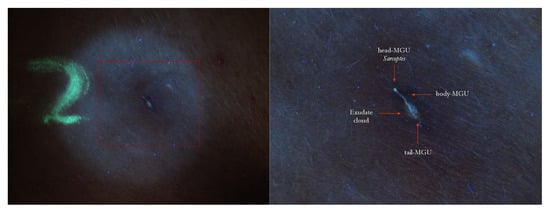

Figure 2.

Flash light vs. UVA. A MGU was already recognizable to naked eye (left) as an apparent single structure. However, UVA light was able to distinguish body-MGU (white wave) from head-MGU (green-dot) where Sarcoptes body was physically located (right). The red phlogosis halo around burrow returned a darker light than the rest of background. A yellow highlighter was used.